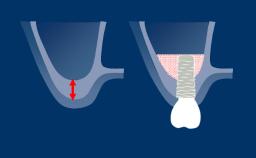

A thorough patient assessment is the basis of any dental treatment plan that may or may not include implants. It is directly related to the treatment outcome.

This ITI Academy module serves as an overview and introduction to the related modules that will discuss each of the components involved in structured patient assessment and treatment planning in detail.